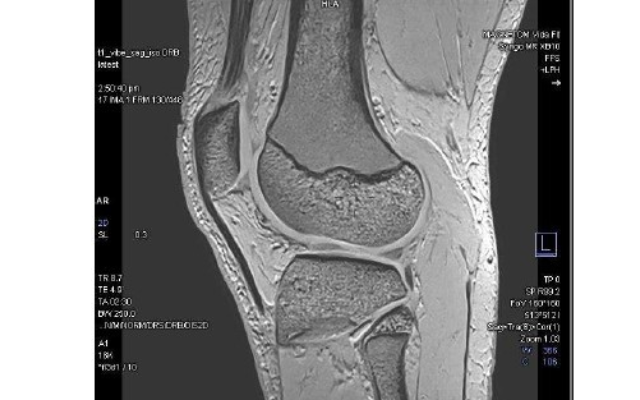

A new state-of-the-art magnetic resonance imaging (MRI) machine was recently installed at the TRG Imaging Kensington clinic. The latest addition will provide faster scan times and better-quality images for patients.

“Faster imaging using the latest technology, combined with the wide bore, and an improved sound system, makes for a more comfortable experience for the patient,” said TRG Imaging Whangārei service manager, Steph Claridge.